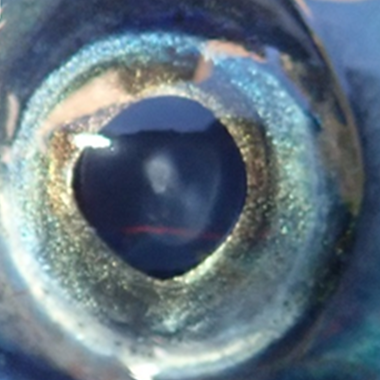

Atlantic salmon eye with minor opacity16

|